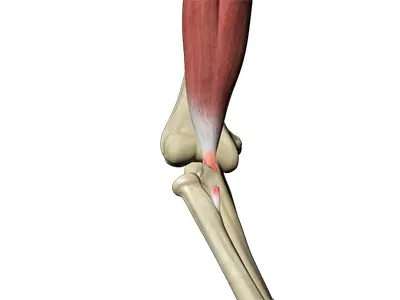

Triceps Injuries

The triceps or triceps brachii is a crucial muscle of the upper arm (humerus). It runs along the upper arm bone between the shoulder and elbow.

Triceps Tendonitis

Triceps tendonitis is inflammation of the triceps tendon, the tissue that connects the triceps muscle on the back of the upper arm to the back of the elbow joint